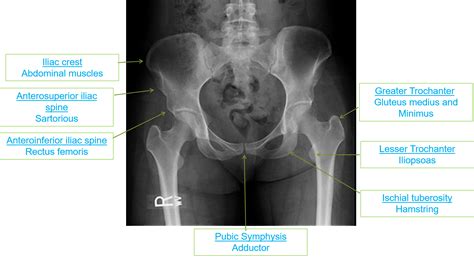

Common sites for these fractures include:

• Ischial Tuberosity: Where the hamstring muscles attach (often during sprinting).

• Anterior Inferior Iliac Spine (AIIS): Where the rectus femoris (part of the quadriceps) attaches (often during kicking or jumping).

• Anterior Superior Iliac Spine (ASIS): Where the sartorius muscle attaches.

• Iliac Crest: Where the abdominal muscles attach.

To grasp why an avulsion fracture in hip anatomy occurs, it is essential to understand the connection between muscles and bones. Muscles attach to bones via tendons. In the hip area, several major muscle groups—including the hamstrings, hip flexors, and abductors—attach to specific bony prominences on the pelvis. When these muscles contract violently or are stretched beyond their limits while already contracted, they can literally "avulse" or tear off a piece of the bone at the point of attachment.